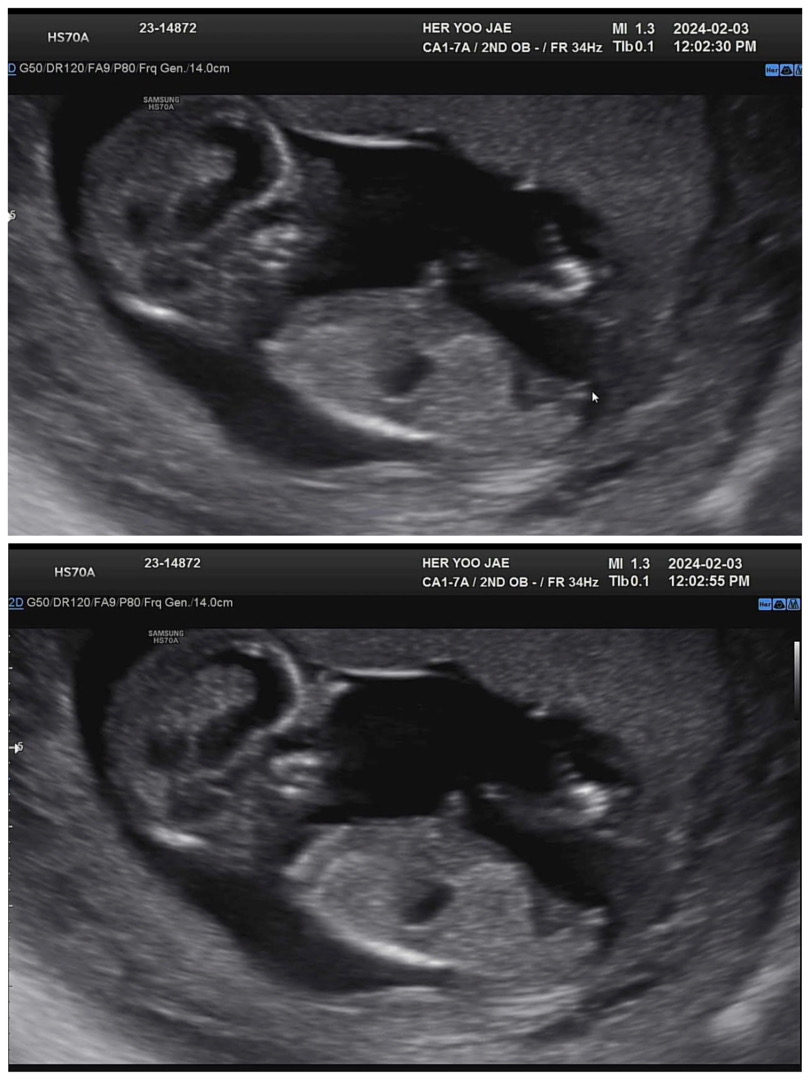

저 아들인거 맞을까용?😭12주 5일차

노산에 체력도 저질이라 딸이였음 하는 바람인데ㅜㅜ 의사샘은 저 밑에를 보며 열심히 연구해보라고 하시며.. 말씀을 아껴주셨눈데ㅜㅜㅜ 왠지 각도법 글들 보니 울 애기는 아들로 보이는 것 같아서요....